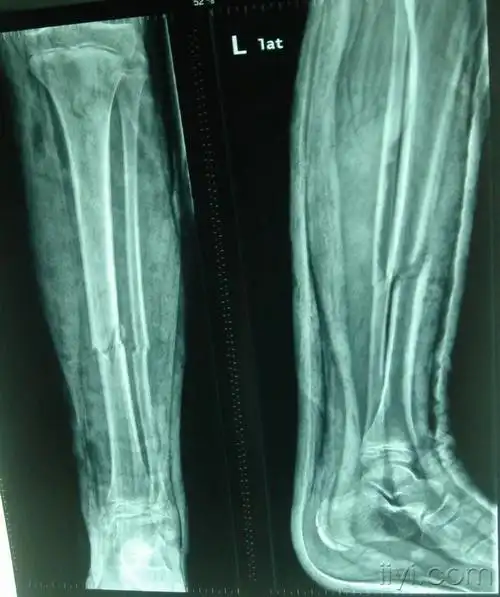

开放性胫腓骨粉碎性多段骨折伴小腿筋膜室综合征

9岁,外伤致做胫腓骨中下段骨折 2018-04-15 2018-06-02骨痂形成

我的胫腓骨粉碎性骨折两个月了!

本人男,19岁,小腿胫骨骨折100天,请大家看看怎么样?

病例讨论14岁男孩左胫腓骨骨折复位石膏外固定后